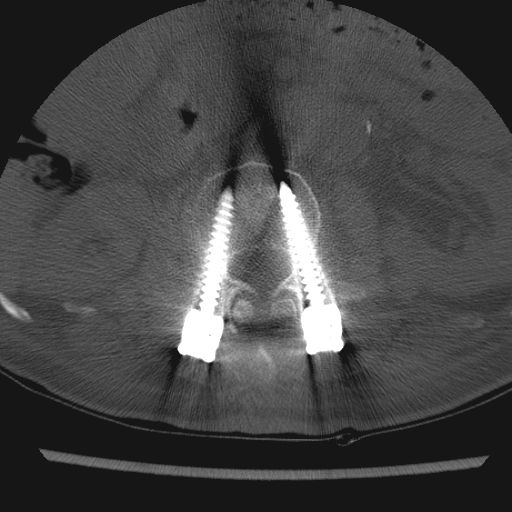

術前術後のレントゲン以下、レントゲン写真を紹介します。「1→」第3腰椎でしょうか、つぶれています。しかし、担当医によればこの部分からの痛みはないようです。 「2→」第1腰椎でしょうか、腹側がささくれています。 又、写真には写っていませんがこの部分の「腰神経叢」滞りがあるようです。 ![]() チタン製のスクリューと固定版を背中側から撮った映像です。 MRで胴体部分を輪切りにした映像です。 縦に3本のスクリューが入れられているのが鮮明に表示されています。 「3→」の部分は避けていた腰椎に人口骨を入れ補強・修正した部分をなります。